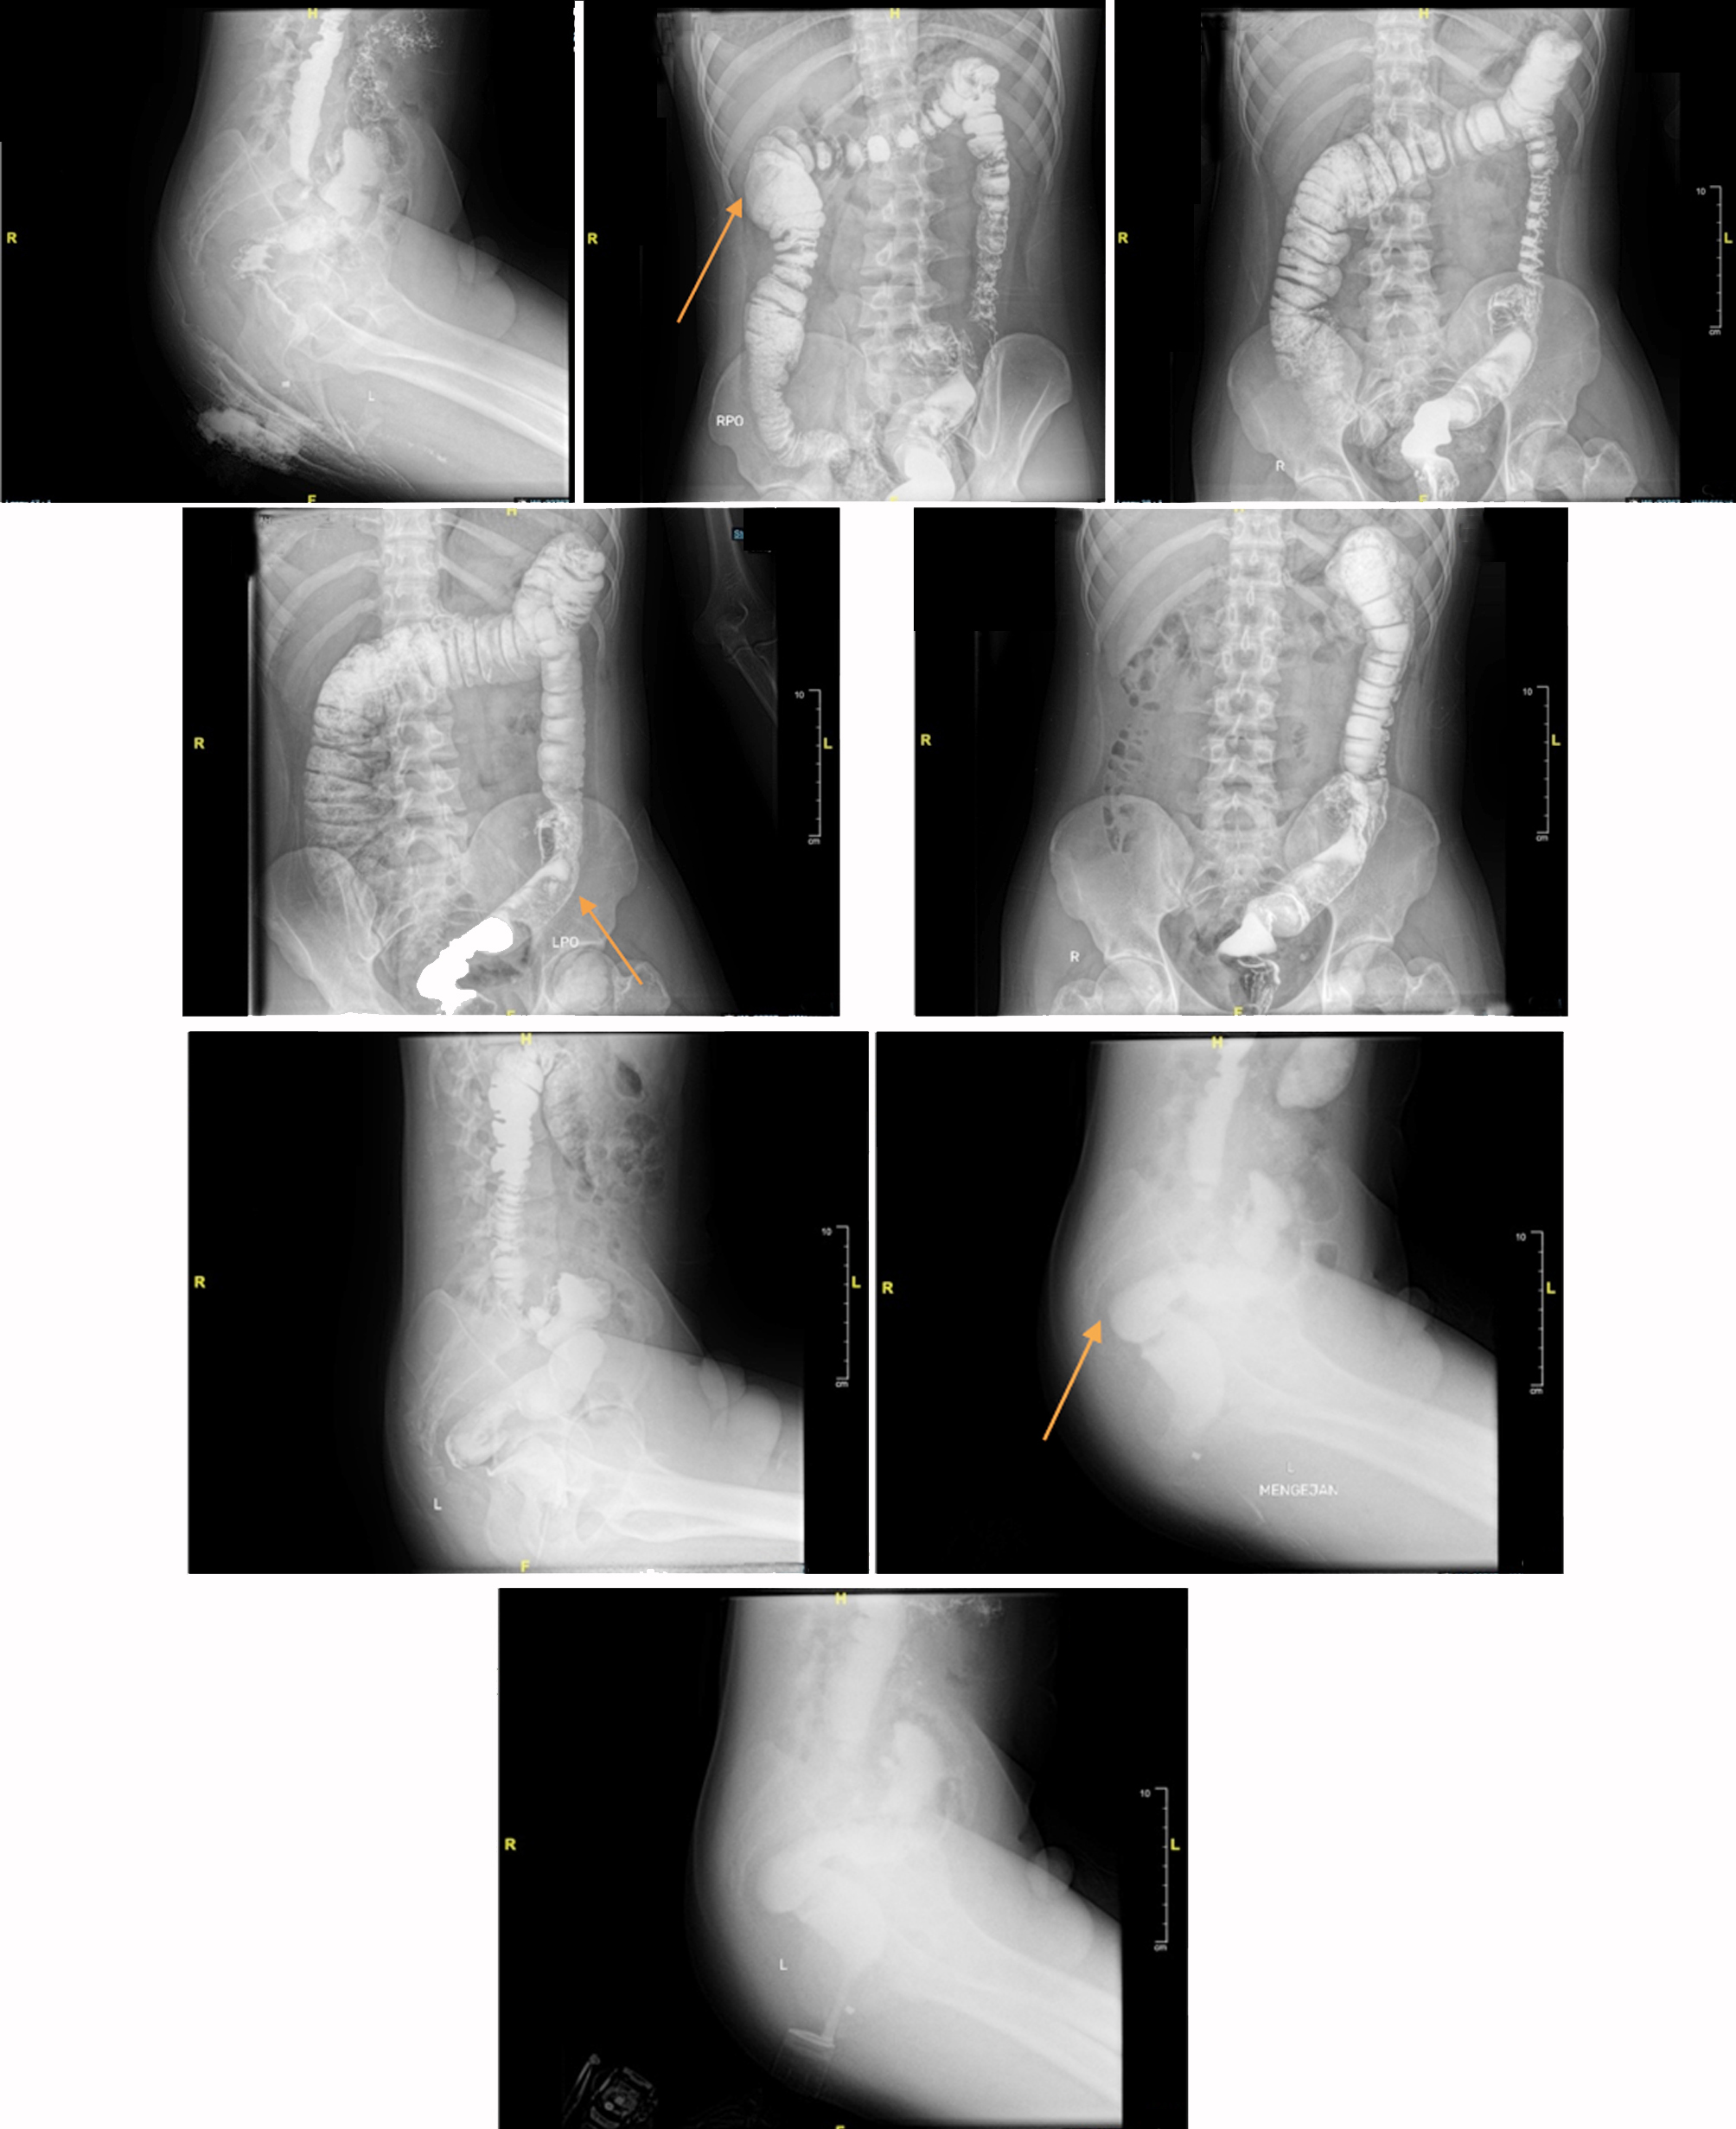

The patient had no difficulty with flatus, and there was no disturbance in urination. Vital signs were within normal limits. Physical abdominal examinations revealed distension but no pain upon palpation, and bowel sounds during auscultation were normal. We consulted the Physical Medicine and Rehabilitation Division to assess the potential for pelvic floor dysfunction, and the results were negative. A barium enema examination was performed to rule out Hirschsprung’s disease. Evaluation of colon structure abnormalities through the barium enema revealed a redundant ascending colon, hepatic flexure, and sigmoid, with no dilatation or filling defects in the colon (fig. 2). A biopsy was also performed, resulting in no aganglionic tissue.

Figure 2 - Barium enema pre-operative (July 2024): redundant ascendence colon, hepatic flexure, and sigmoid with no dilatation of colon

A barium enema evaluation was performed two months post-operative. The results showed no significant stenosis or filling defect in the visualized colon, with no visible redundancy of the sigmoid (fig. 3).

Figure 3 - Barium enema post-operative (September 2024): no stenosis and filling defect on the visualized colon with no visible redundancy of the sigmoid compared to pre-operative (shown with the orange arrow).